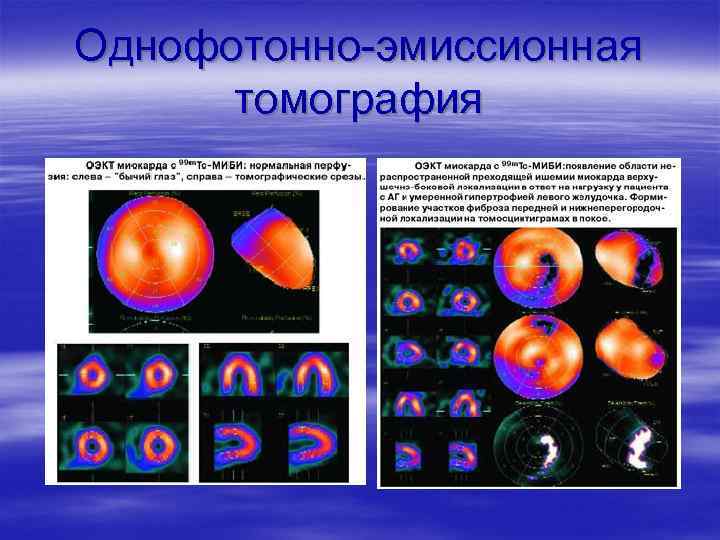

Однофотонно-эмиссионная томография

Однофотонно-эмиссионная томография